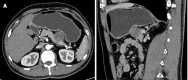

Case summary: We report on a rare case of CCS with pancreatic metastasis in a 47-year-old man. The patient had a relevant medical history 3 years ago, with abdominal pain as the main clinical manifestation. No abnormalities were observed on physical examination and the tumor was found on abdominal computed tomography. Based on the medical history and postoperative pathology, the patient was diagnosed with CCS with pancreatic metastasis. The patient was successfully treated with surgical interventions, including distal pancreatectomy and splenectomy.